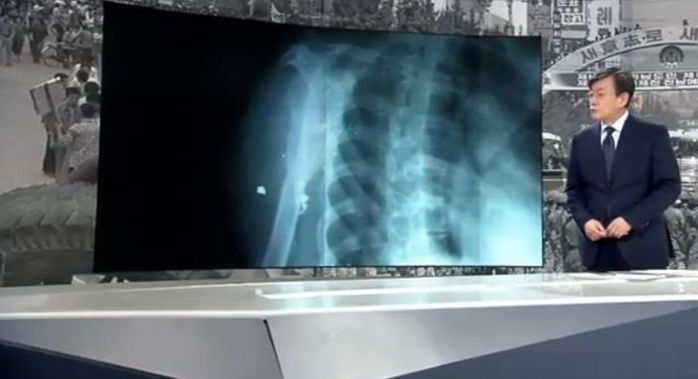

[인사이트] 장형인 기자 = 과거 5·18 당시 계엄군이 쏜 총에 맞은 시민들이 37년이 지나도 여전히 아픈 몸을 안고 살고 있는 것으로 확인됐다. 지난 28일 JTBC 뉴스는 5·18 부상자회에 등록된 총상 피해 환자 42명 중 29명이 수술도 못 받아 파편을 안고 살고 있다...

5·18 계엄군한테 맞은 납탄 파면 ‘37년’ 동안 몸에 안고 사는 시민들